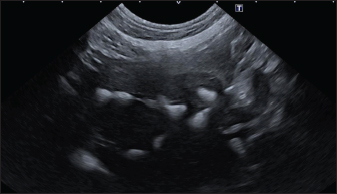

In the aligned pattern, mineralization foci are often millimetric, rarely sub-centimetric, forming isolated linearities in the hepatic parenchyma, without a real branching pattern, seeming to follow the course of some intrahepatic biliary ducts (Fig. 2). Sub-centimetric and centimetric IBTM determined a focal dilatation of the biliary ducts in 34.4% of dogs (11/32). In eight of these subjects (25%), we also found millimetric IBTM randomly distributed in the liver.

Fig. 2. Ultrasound image of the liver showing millimetric IBTM not generating acoustic shadow, with an aligned pattern.